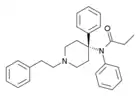

Anilidopiperidines